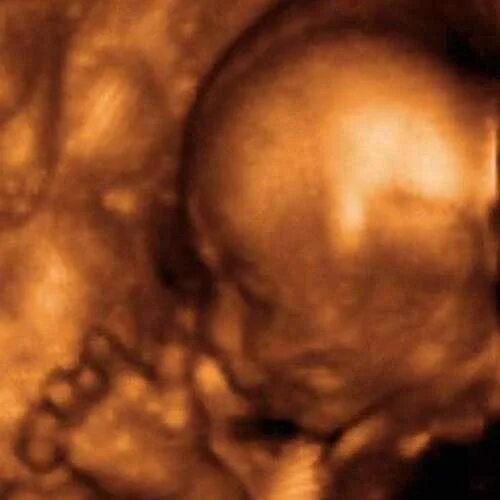

Сейчас 23 недели